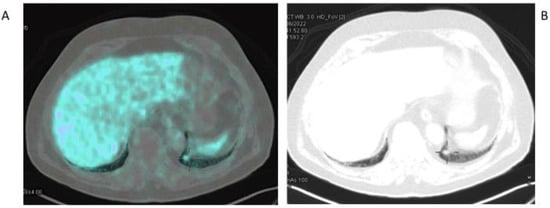

- Kesler, M.; Levine, C.; Hershkovitz, D.; Mishani, E.; Menachem, Y.; Lerman, H.; Zohar, Y.; Shibolet, O.; Even-Sapir, E. 68Ga-PSMA is a novel PET-CT tracer for imaging of hepatocellular carcinoma: A prospective pilot study. J. Nucl. Med. 2019, 60, 185–191. [Google Scholar] [CrossRef] [PubMed]

- Kuyumcu, S.; Has-Simsek, D.; Iliaz, R.; Sanli, Y.; Buyukkaya, F.; Akyuz, F.; Turkmen, C. Evidence of prostate-specific membrane antigen expression in hepatocellular carcinoma using 68Ga-PSMA PET/CT. Clin. Nucl. Med. 2019, 44, 702–706. [Google Scholar] [CrossRef] [PubMed]

- Gündoğan, C.; Ergül, N.; Çakır, M.S.; Kılıçkesmez, Ö.; Gürsu, R.U.; Aksoy, T.; Çermik, T.F. 68Ga-PSMA PET/CT versus 18F-FDG PET/CT for imaging of hepatocellular carcinoma. Mol. Imaging Radionucl. Ther. 2021, 30, 79. [Google Scholar] [CrossRef] [PubMed]

- Hirmas, N.; Leyh, C.; Sraieb, M.; Barbato, F.; Schaarschmidt, B.M.; Umutlu, L.; Nader, M.; Wedemeyer, H.; Ferdinandus, J.; Rischpler, C.; et al. 68Ga-PSMA-11 PET/CT improves tumor detection and impacts management in patients with hepatocellular carcinoma. J. Nucl. Med. 2021, 62, 1235–1241. [Google Scholar] [CrossRef]